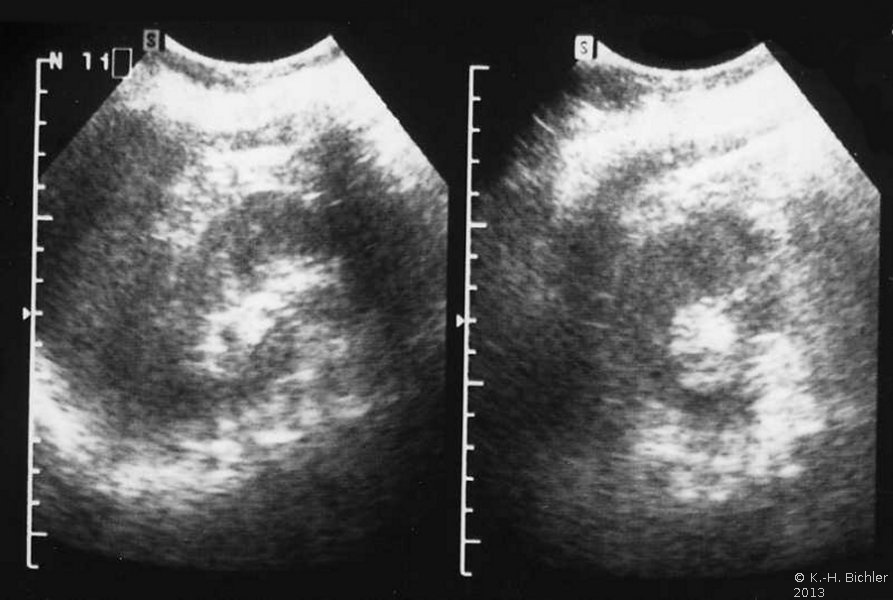

Neben der Anamnese, körperlicher Untersuchung, Messung des Blutdruckes sowie der Laboruntersuchungen: Urinstatus, Serumkreatinin und -Elektroylte ist die Sonographie zur Feststellung einer einseitig kleinen Niere zielführend (Abbildung 10a). Zur Diagnostik zählt fernerhin die NFZG (Abbildung 10b) bzw. Computertomographie.

Computertomographie zur Diagnostik der kleinen Niere. Zum Beispiel eine pyelonephritisch veränderte linke Niere im Computertomogramm und im weiteren Beispiel CT und Organpräparat einer rechtsseitigen kleinen Niere.

Und in einem weiteren Beispiel CT und Organpräparat einer rechtseitigen "kleinen Niere" (Abbildung 11, 12ab).